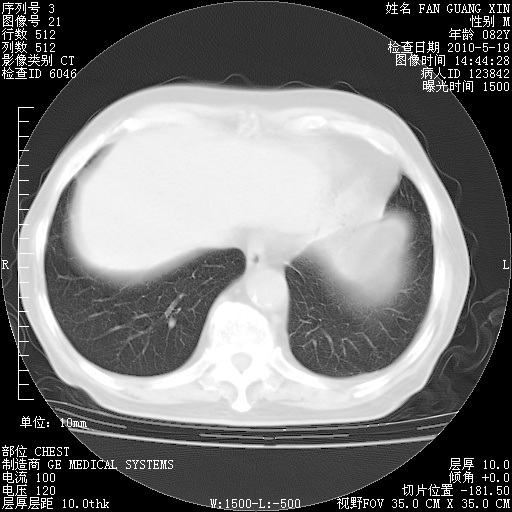

治疗3周后的肺部CT

治疗3周后的肺部CT纵隔窗